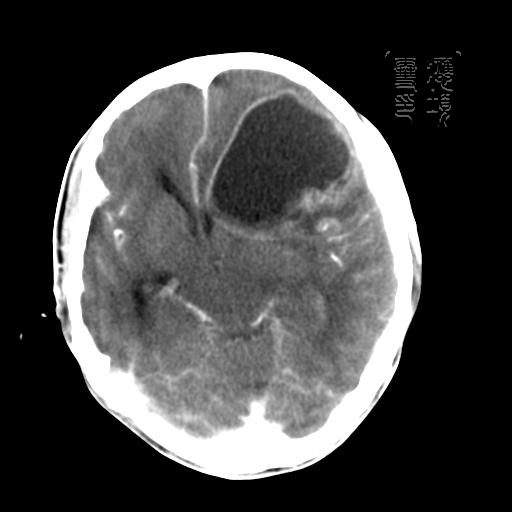

m 52y

二月前癫痫入院, 无既往史,现头痛、呕吐、视力减退、复视行ct平扫及增强检查。

见环形,结节样强化,考虑囊性星型细胞瘤。

考虑囊性星型细胞瘤,ct征象大囊小结节.

左额叶囊实性占位,以囊性为主,并见明显强化不规则壁结节,占位效应明显,首先考虑是囊性星形细胞瘤.

从发病部位及年龄都不考虑是血管母细胞瘤,还有可能是胶质瘤.

可能为左额叶恶性胶质母细胞瘤。

胶质母细胞瘤的花边状强化及出血的特点这组片中没体现出来.还是支持囊性星型细胞瘤.